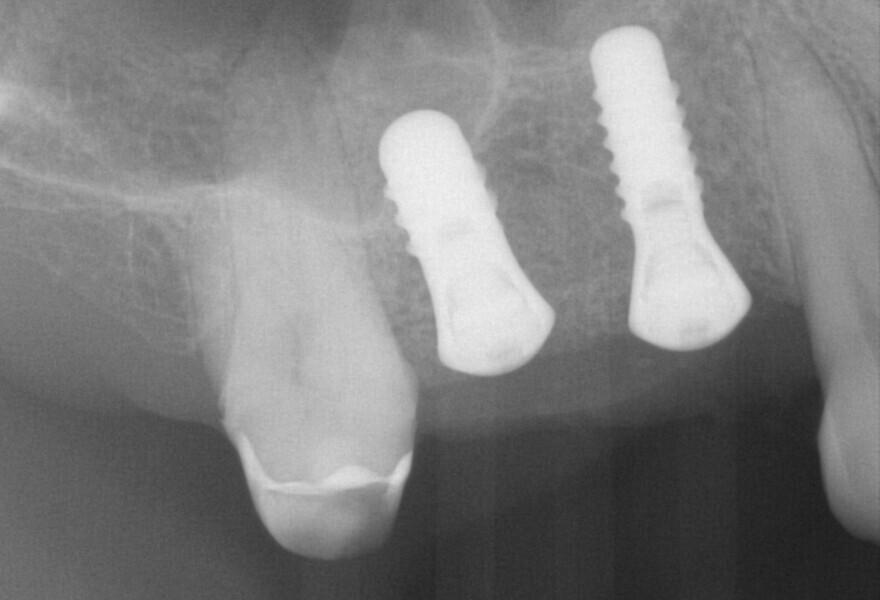

Fig. 12: Post-op radiograph showing the implants in regions #14 and 15.